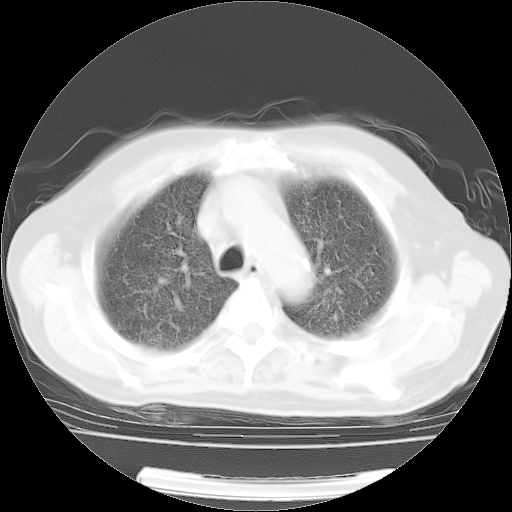

4月14日肺部CT